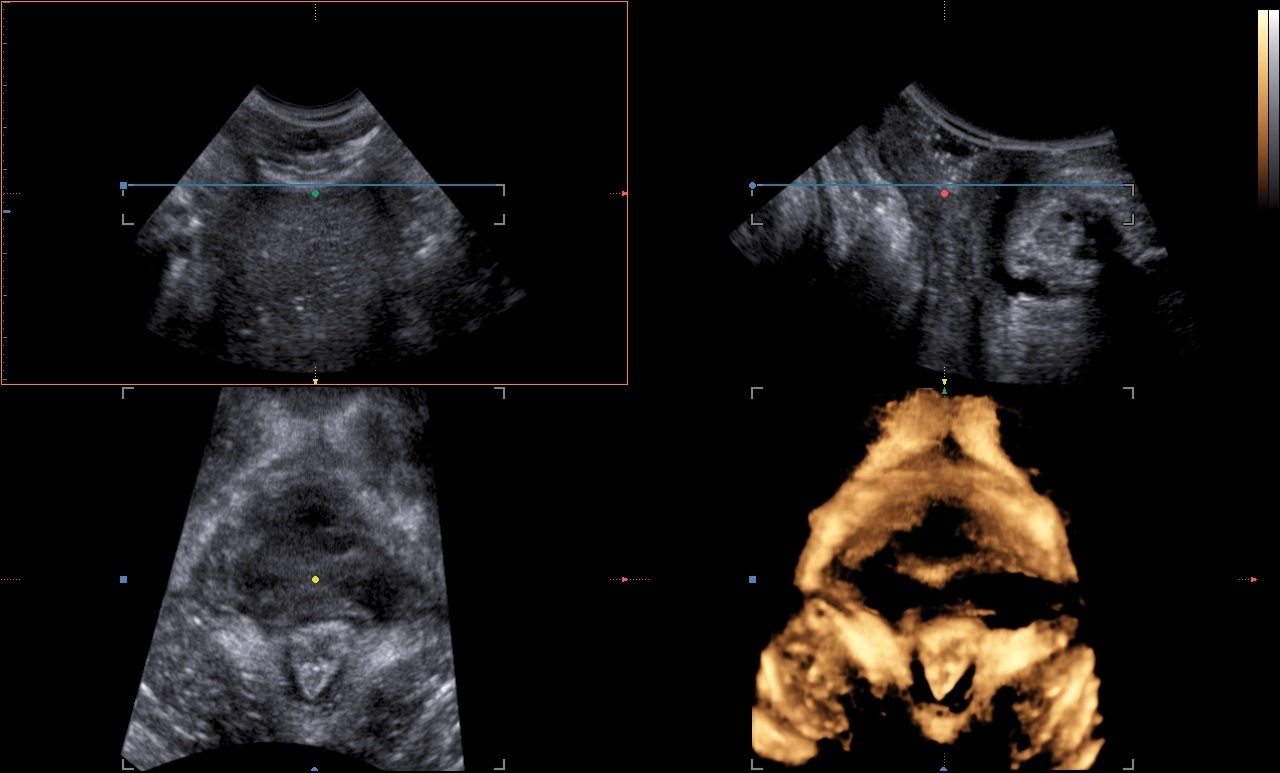

The levator ani muscle avulsion may be demonstrated with 2D Ultrasound, however 3D (or even 4D) Ultrasound as well as MRI are superior in demonstrating avulsion (Dietz 2019).